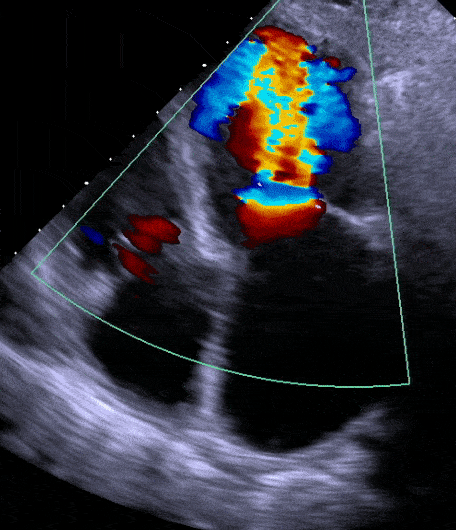

The lecture discussed the current state of AI in Healthcare, focusing on medical imaging and how it may augment a cardiologist's expertise and practice. The goal, of course, is to match or indeed outperform the clinician's/expert's performance here (the latter being the Gold Standard). The assertion was that it will fundamentally transform this field over the next few years. The example supplied was ValveNet, a model that attempts to predict Valvular Heart Disease (VHD) using Deep Learning[^1]. The model uses data from Electrocardiography (ECG/EKG) which is different from Echocardiography. The former is familiar: you apply probes to the patient's chest and get the QRS graphs ("Complex"[2]). The latter involves ultrasound and is more time-consuming and expensive (a kind of sonogram for the heart; very visual). The goal of the model (which indeed fits into the larger goal of AI in Healthcare) then, is to use cheaper and common (yet noisy?) data generation techniques to match the accuracy one would obtain from expensive and inaccessible solutions: Cardiologists cannot just use Electrocardiograms to diagnose VHD! EchoNet (2005)[3], "trained on more than 1 million heart rhythm and imaging records" using Deep Learning techniques has shown very high diagnostic accuracy and outperformed experts and is a promising sign of the potential of AI in medicine.